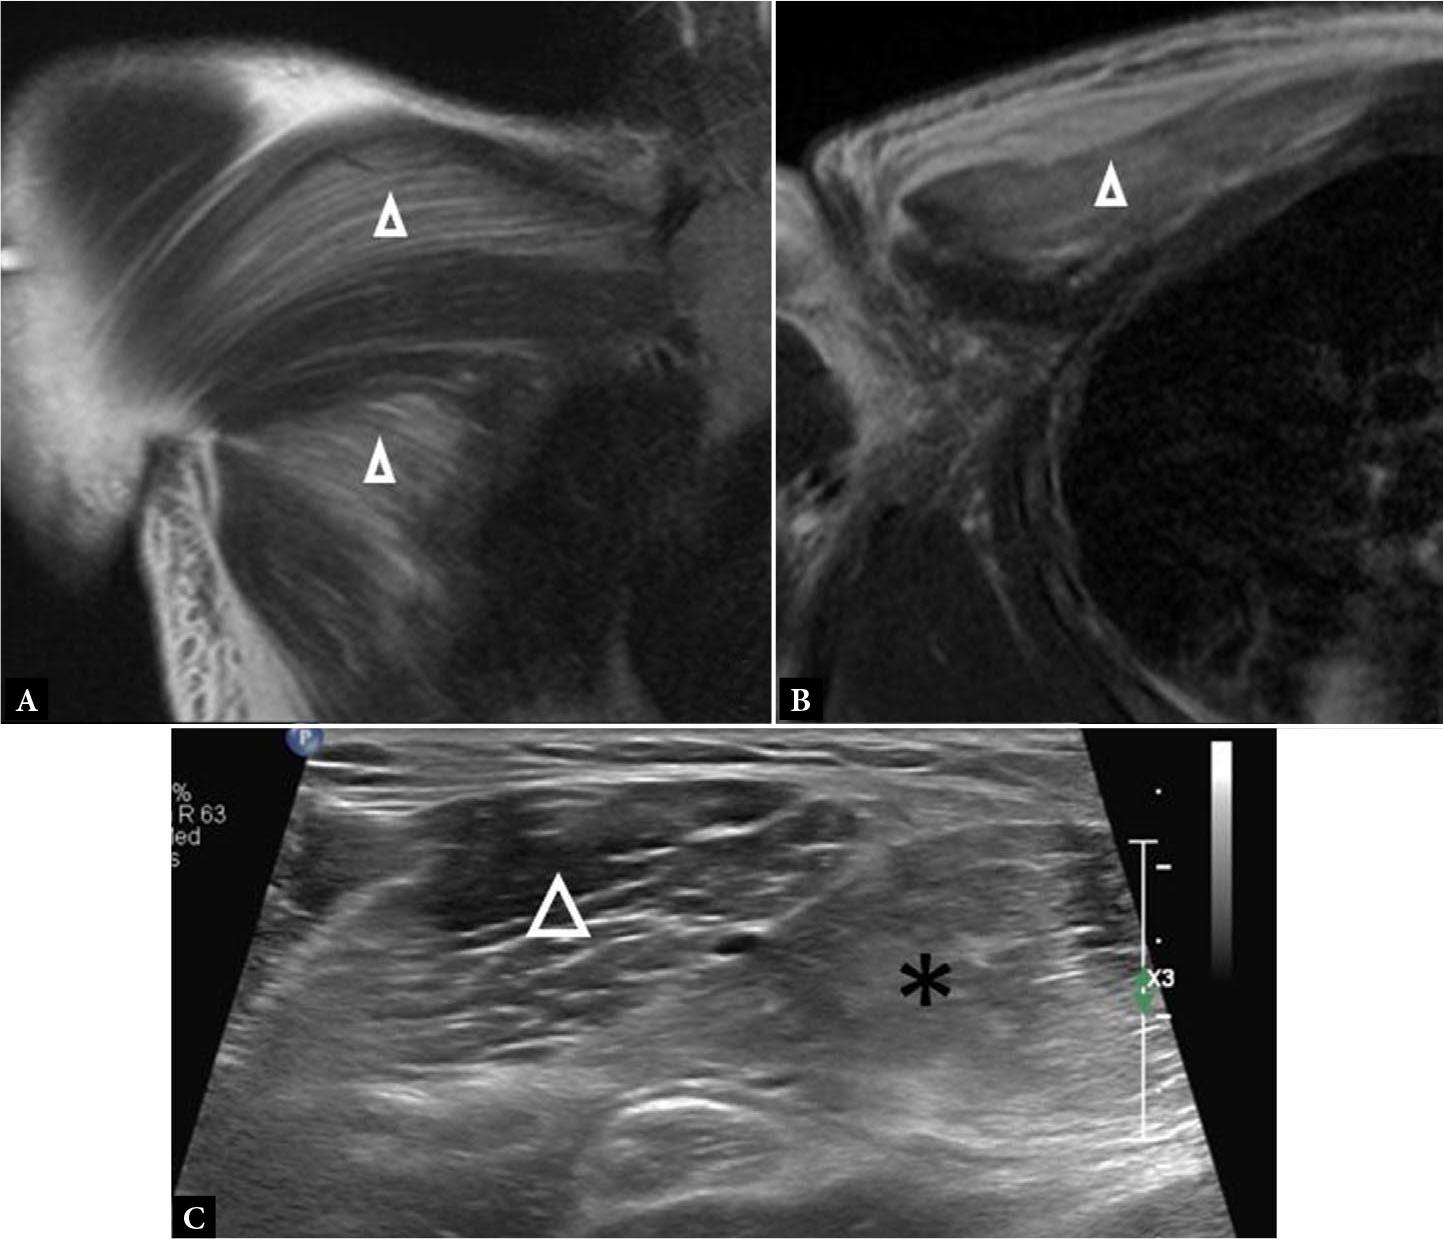

Fig. 14.

Coronal (A) and axial (B) fluid-sensitive MR images show diffuse, feathery signal hyperintensity in the PM muscle (open arrowheads) without fiber disorganization or laxity, consistent with PM strain. C. Long axis gray scale ultrasound image in another patient demonstrates increased echogenicity and poorer fiber conspicuity in a patient with strain of the clavicular head of the PM (asterisk). Note the normal architecture of the adjacent deltoid muscle (arrowhead). There is no frank fiber disruption or disorganization in these images to suggest tear